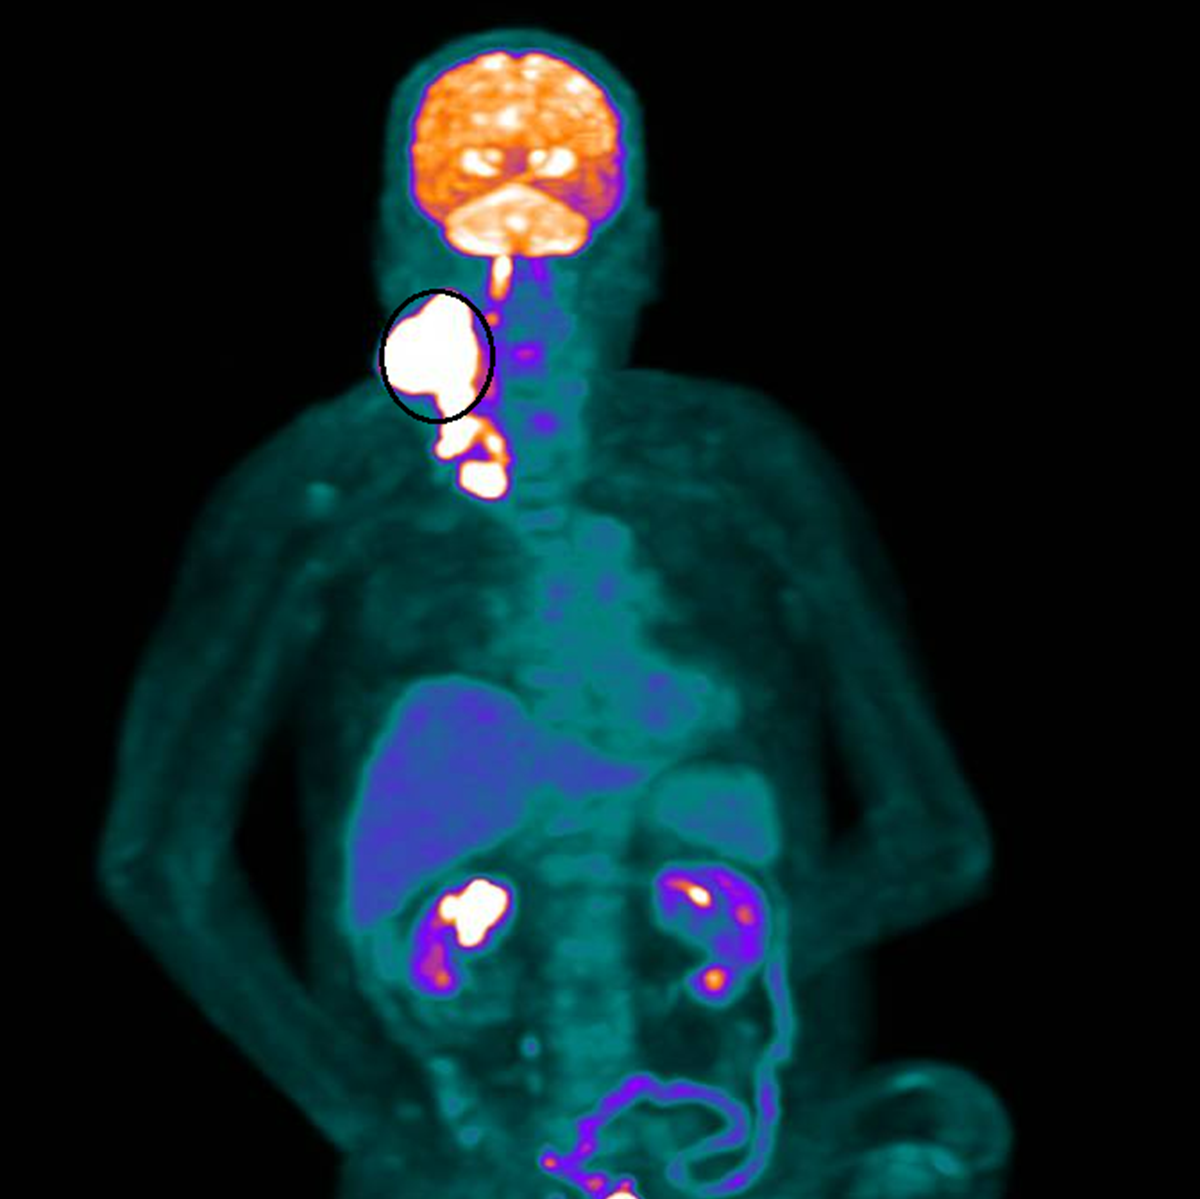

林先生隨即展開為期兩個月、共35次俗稱「電療」的放射線治療。療程結束後,原本巨大、外觀明顯的腫瘤幾乎完全消失,治療反應遠超預期。這個結果,不僅讓醫療團隊振奮,也為家屬帶來久違的笑容。